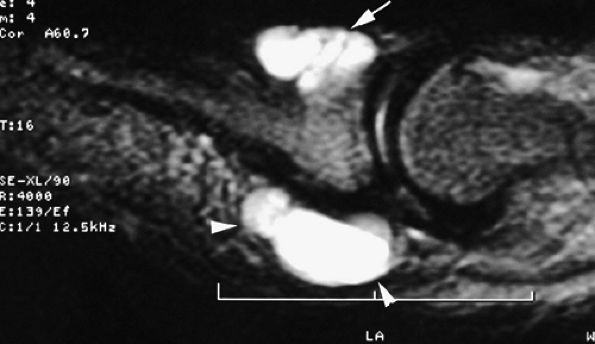

FIGURE 11.47 ● Jersey finger. (A) Sagittal T2-weighted image. (B) Coronal post-contrast T1-weighted images. (C) Axial T1-weighted image. Distal avulsion of the FDP tendon is shown with the proximal end (white arrows) at the metacarpophalangeal joint (type I). The tendon is wavy in the palm (arrowheads). The empty digital canal (in C) may mimic a remnant tendon, but the FDS tendon (asterisk) is alone in the canal.